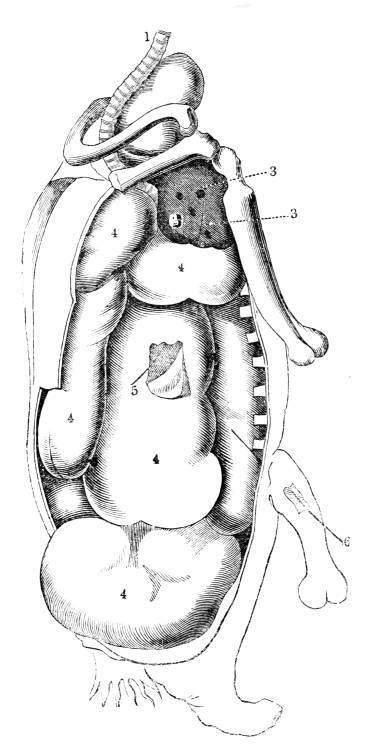

Fig. CXXXIV.—

View of the Respiratory Apparatus in

Man.

1. The Trachea. 2. The right lung. 3. The left lung.

4. Fissures, dividing each lung into, 5. Large portions

termed lobes. 6. Smaller divisions termed lobules. 7.

Pericardium. 8. Heart. 9. Aorta. 10. Diaphragm separating

the cavity of the thorax from that of the abdomen.

357. In man there are two pulmonary bags (fig.

CXXXIV. 2, 3), of nearly equal size, which, together

with the heart, completely fill the large cavity

of the thorax (fig. CXXXIV.), their external surface

being everywhere in immediate contact with

the thoracic walls. One of these bags is placed on

the right side of the body, constituting the right

lung (fig. CXXXIV. 2), and the other on the left,

constituting the left lung (fig. CXXXIV. 3). Each

lung is divided by deep fissures, into large portions

called lobes (figs. CXXXIV. 4, and CXXXV.

6), of which there are three belonging to the

right, and two to the left lung. Each lobe is

subdivided into innumerable smaller parts termed

lobules (figs. CXXXIV. 6, and CXXXV. 6), while the

lobules successively diminish in size until they

terminate in minute vesicles that constitute the

great bulk of the organ (fig. CXXXV. 8).